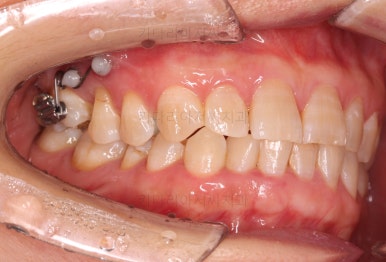

부산교정치료 전후사진을 비교해 보겠습니다.

쓰러진 치아도 원위치로 만들어 기능을 회복시켜주었고, 임플란트도 1개로 마무리를 할 수 있었어요.

이렇게 단순히 임플란트를 해야 하는 상황도 간단한 교정치료와 병행한다면 치아도 아끼고 임플란트도 줄이는 매우 좋은 치료가 될 수 있답니다.